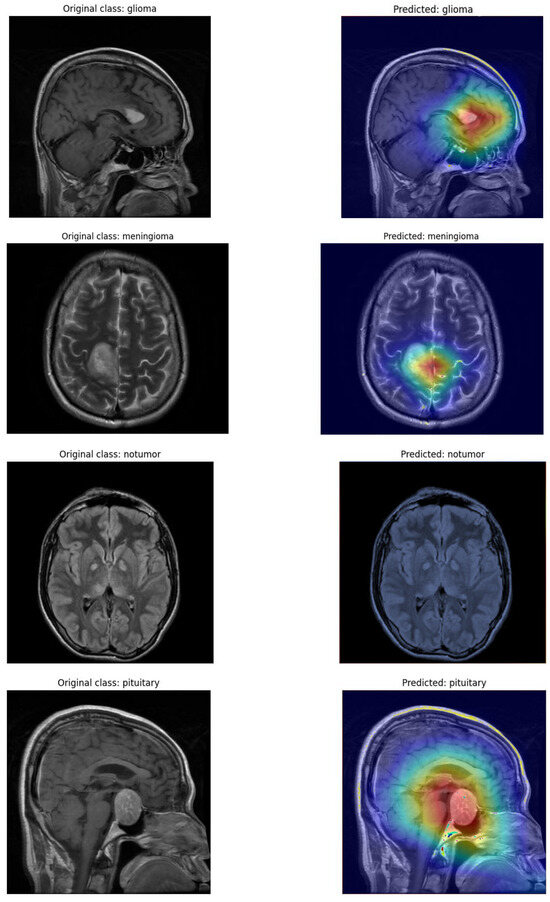

- The model’s explainability through t-SNE plots shows distinct tumor clusters and Grad-CAM highlights crucial areas in MRI scans.

4.5. Confusion Matrix and Visualization